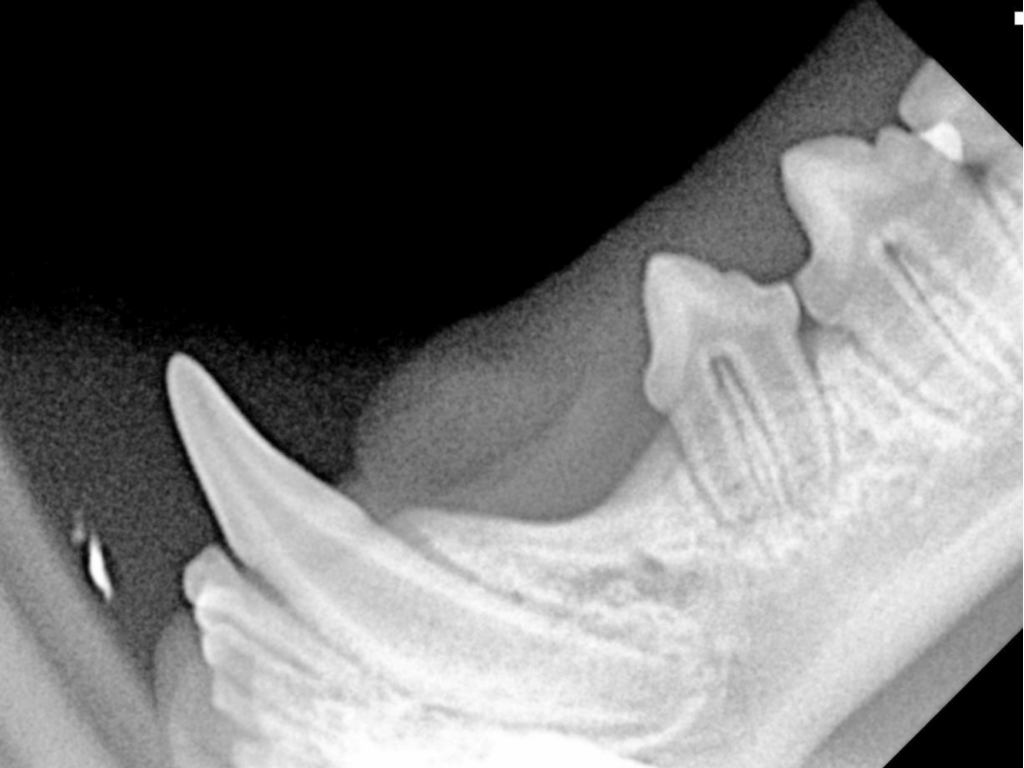

Esta adquisición está destinada a brindar un apoyo fundamental al servicio de Odontología del hospital. La radiografía digital portátil permite obtener imágenes de alta resolución de manera rápida y eficiente, lo que es crucial para un diagnóstico preciso al identificar patologías no visibles a simple vista.